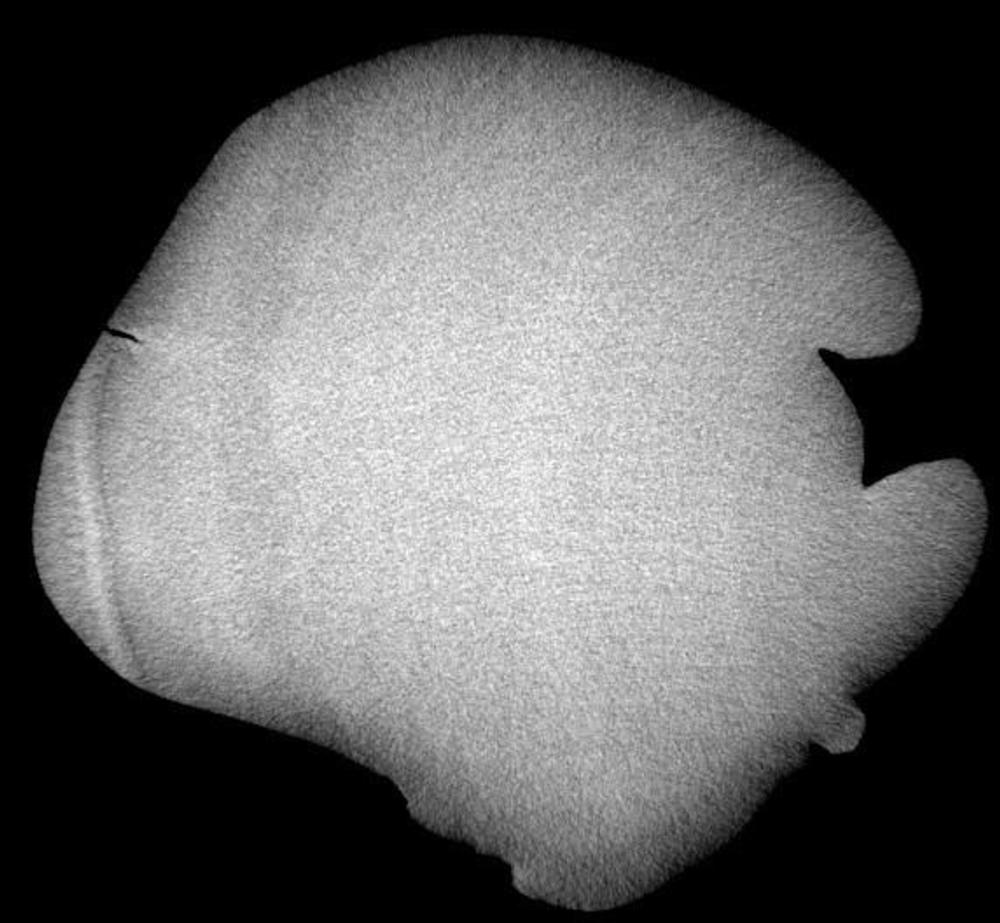

Figure 4. Micro-CT cross section of the manikin at shoulder level, showing one of the arm hinges held in place with higher density ("whiter") material, likely a form of glue.

High-res (TIF) version

Figure 5. Micro-CT cross-sectional image of a manikin made of authentic ivory.